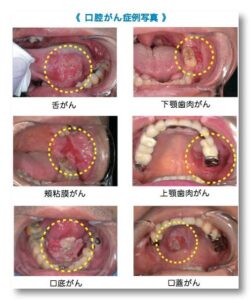

口腔ガンの中でも半数は、舌にできますが、他には頬粘膜、歯肉、口腔底、口蓋など、発症部位は様々です。

症例写真をお乗せしますが、少し過激に感じる方もいると思うので苦手な方はここでご遠慮ください。